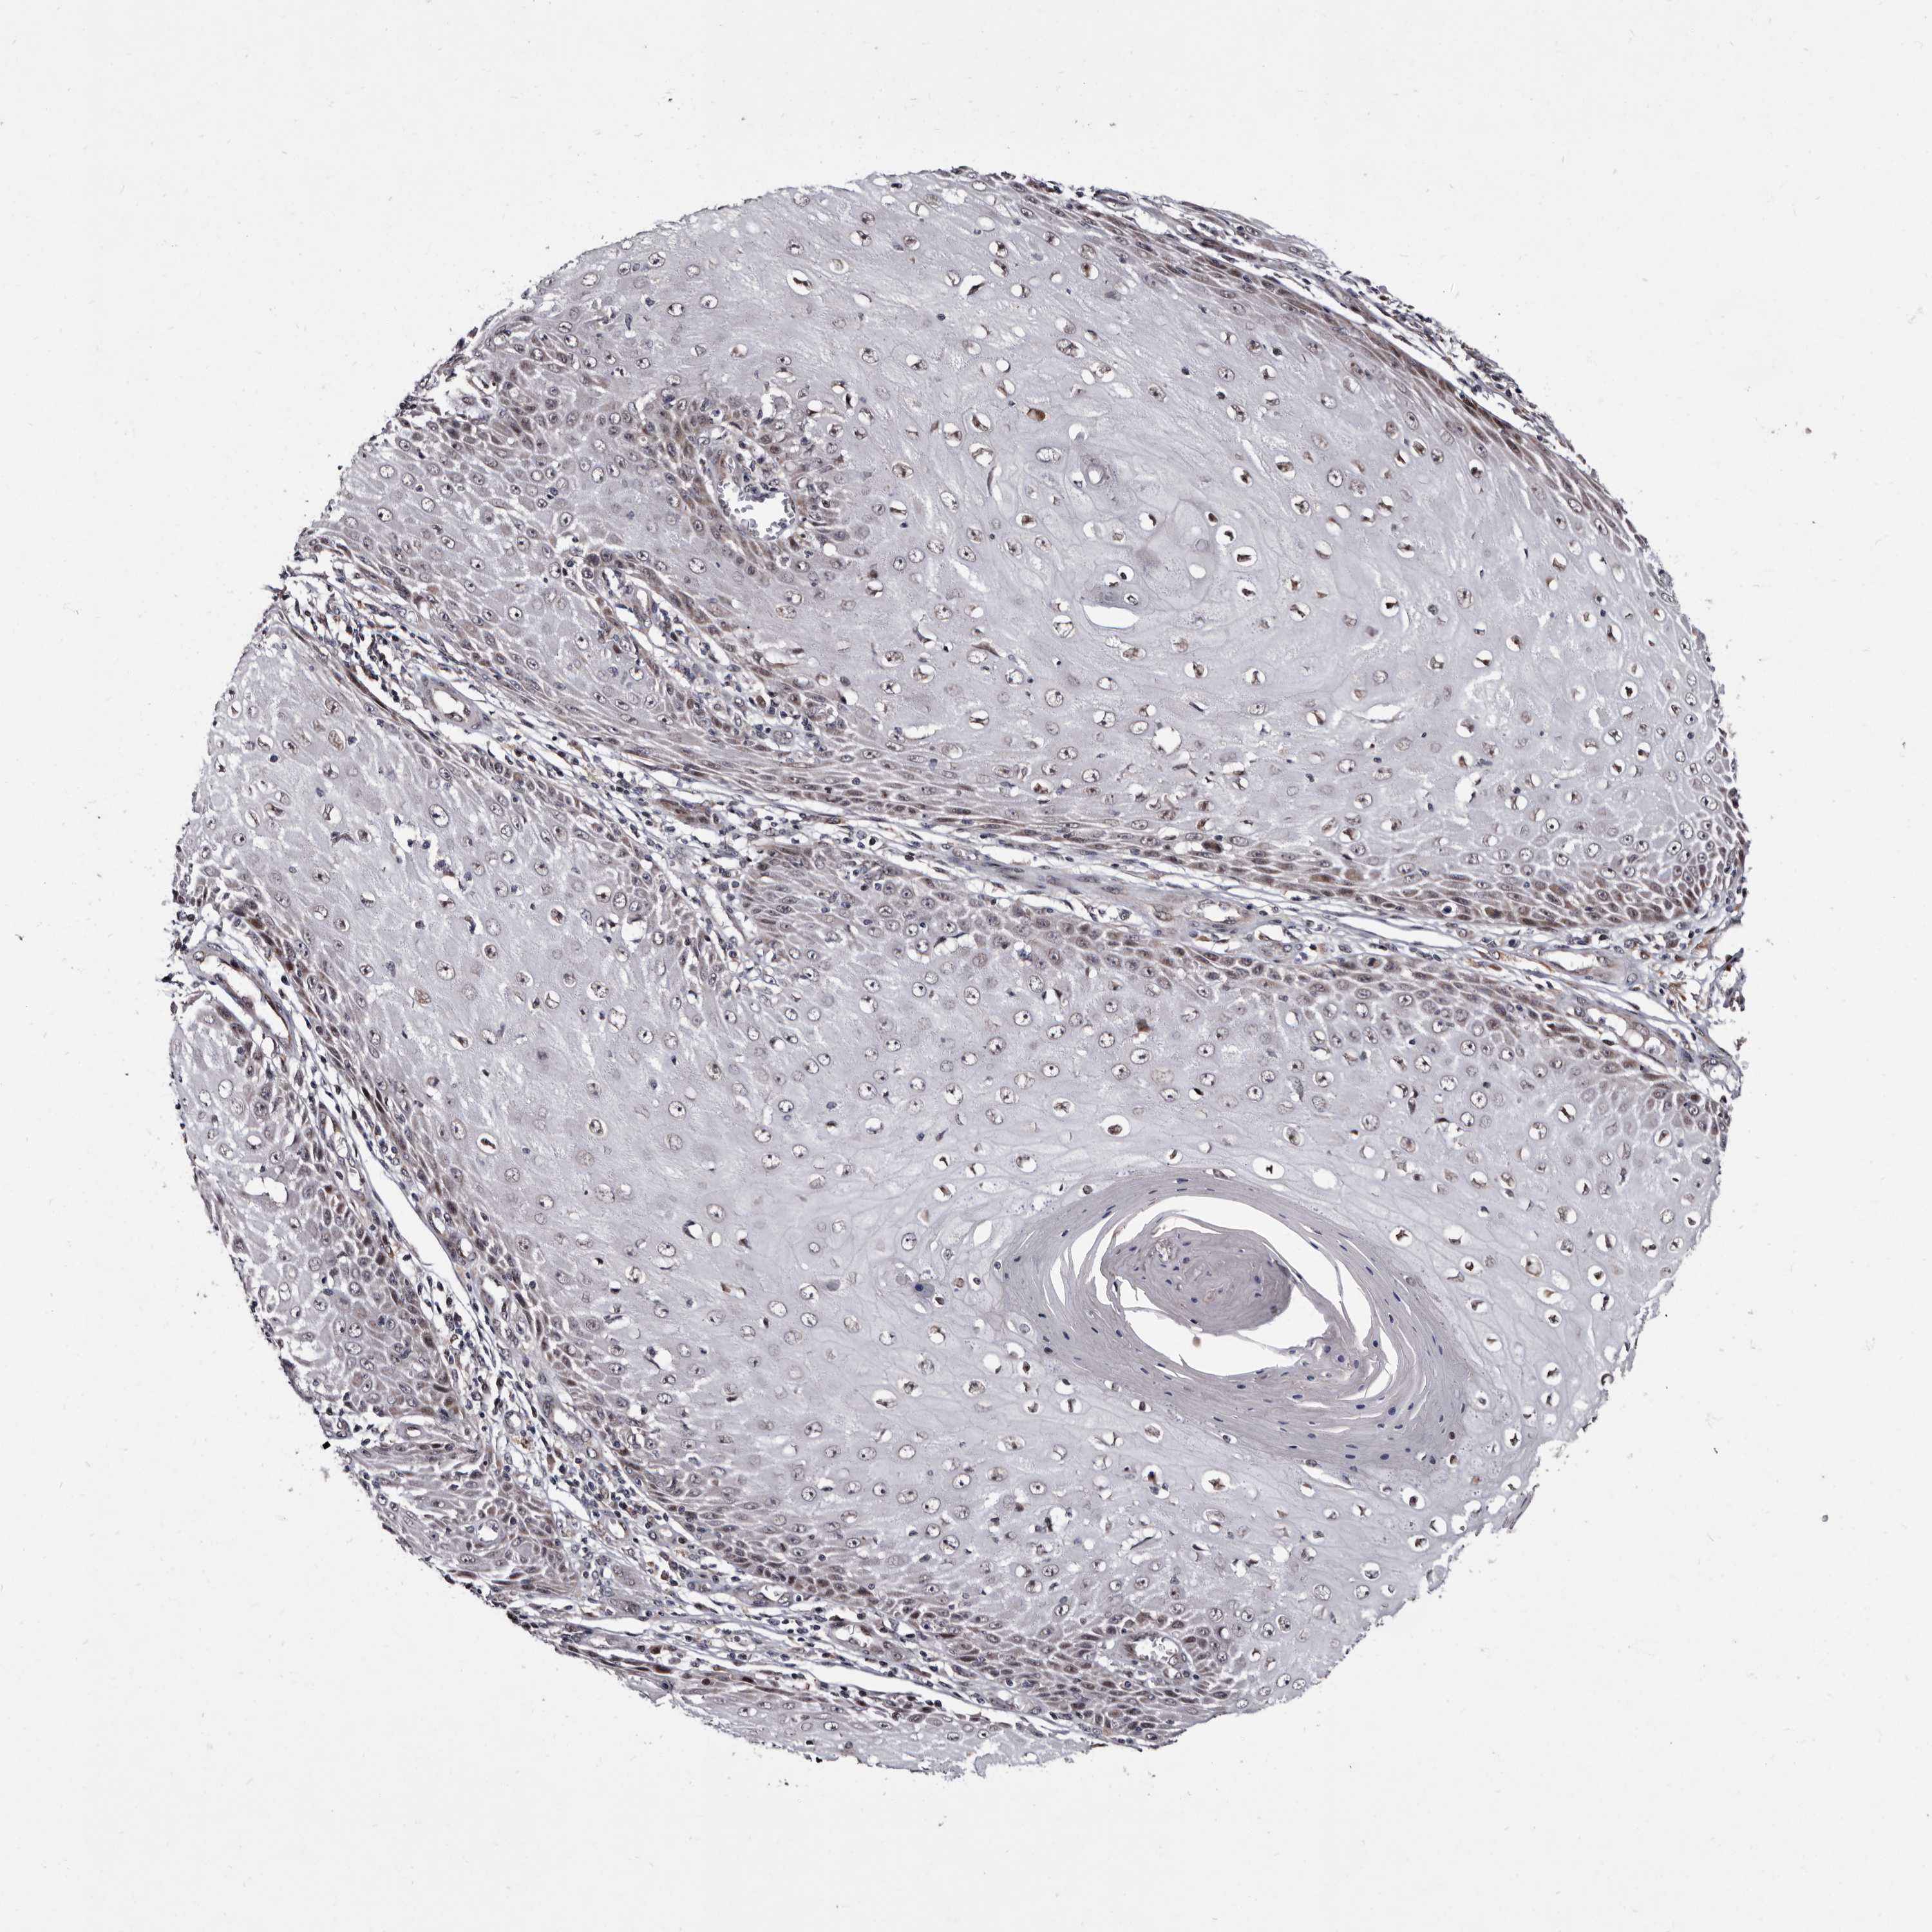

CANCER SKIN CANCER Show tissue menu

Basal cell and squamous cell cancer

SKIN CANCER - Protein expressioni

A mouse-over function shows sample information and annotation data. Click on an image to view it in a full screen mode. Samples can be filtered based on level of antibody staining by selecting one or several of the following categories: high, medium, low and not detected. The assay and annotation is described here.

Each image is clickable and will lead to virtual microscopy that enables deeper exploration of all samples and also displays staining intensity scores, fraction scores and subcellular localization as well as patient and tissue information for each sample.

Antibody HPA025690

Staining

High

Medium

Low

Not detected

Intensity

Strong

Moderate

Weak

Negative

Quantity

>75%

75%-25%

<25%

None

Location

Nuclear

Cytoplasmic/membranous

Cytoplasmic/membranous,nuclear

Basal cell carcinoma

Squamous cell carcinoma, NOS

Squamous cell carcinoma, metastatic, NOS